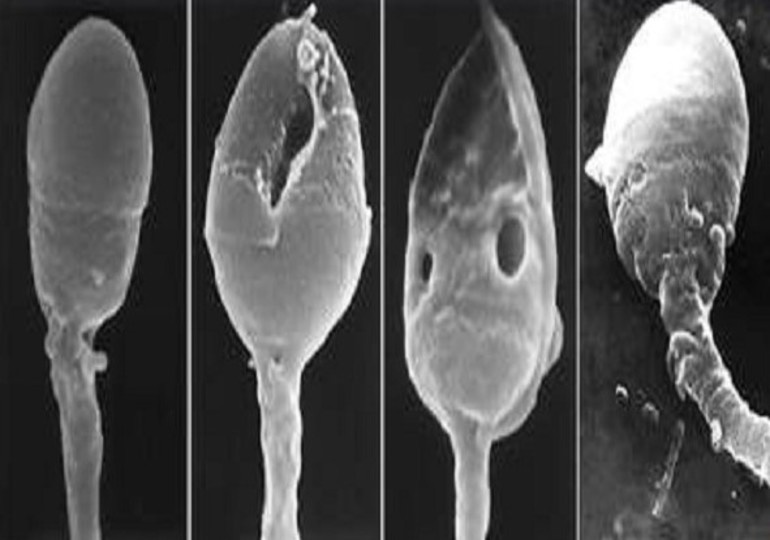

• Доля сперматозоидов с нормальной морфологией уменьшается на 2%.

Курение — это не только вред для лёгких, но и серьёзный удар по мужскому здоровью, включая репродуктивную функцию. Исследования показывают, что курение значительно ухудшает качество спермы, что влияет на вероятность зачатия. 🔬Качество спермы: • В среднем у курящих мужчин концентрация сперматозоидов снижается (https://pmc.ncbi.nlm.nih.gov/articles/PMC11245581/) на 7 млн/мл по сравнению с некурящими. • Мотильность сперматозоидов (их подвижность) падает на 13%. • Доля сперматозоидов с нормальной морфологией уменьшается на 2%. 🧬ДНК-урон: У курильщиков увеличивается количество повреждённых ДНК в сперматозоидах, что может привести к проблемам с эмбриональным развитием и повышенным рискам выкидыша. 🌬️Оксидативный стресс: Курение вызывает образование (https://pmc.ncbi.nlm.nih.gov/articles/PMC10890002/) активных форм кислорода (ROS), которые повреждают мембраны сперматозоидов и снижают их функциональность. 🚨 Риски для зачатия: • Вероятность бесплодия выше (https://pmc.ncbi.nlm.nih.gov/art